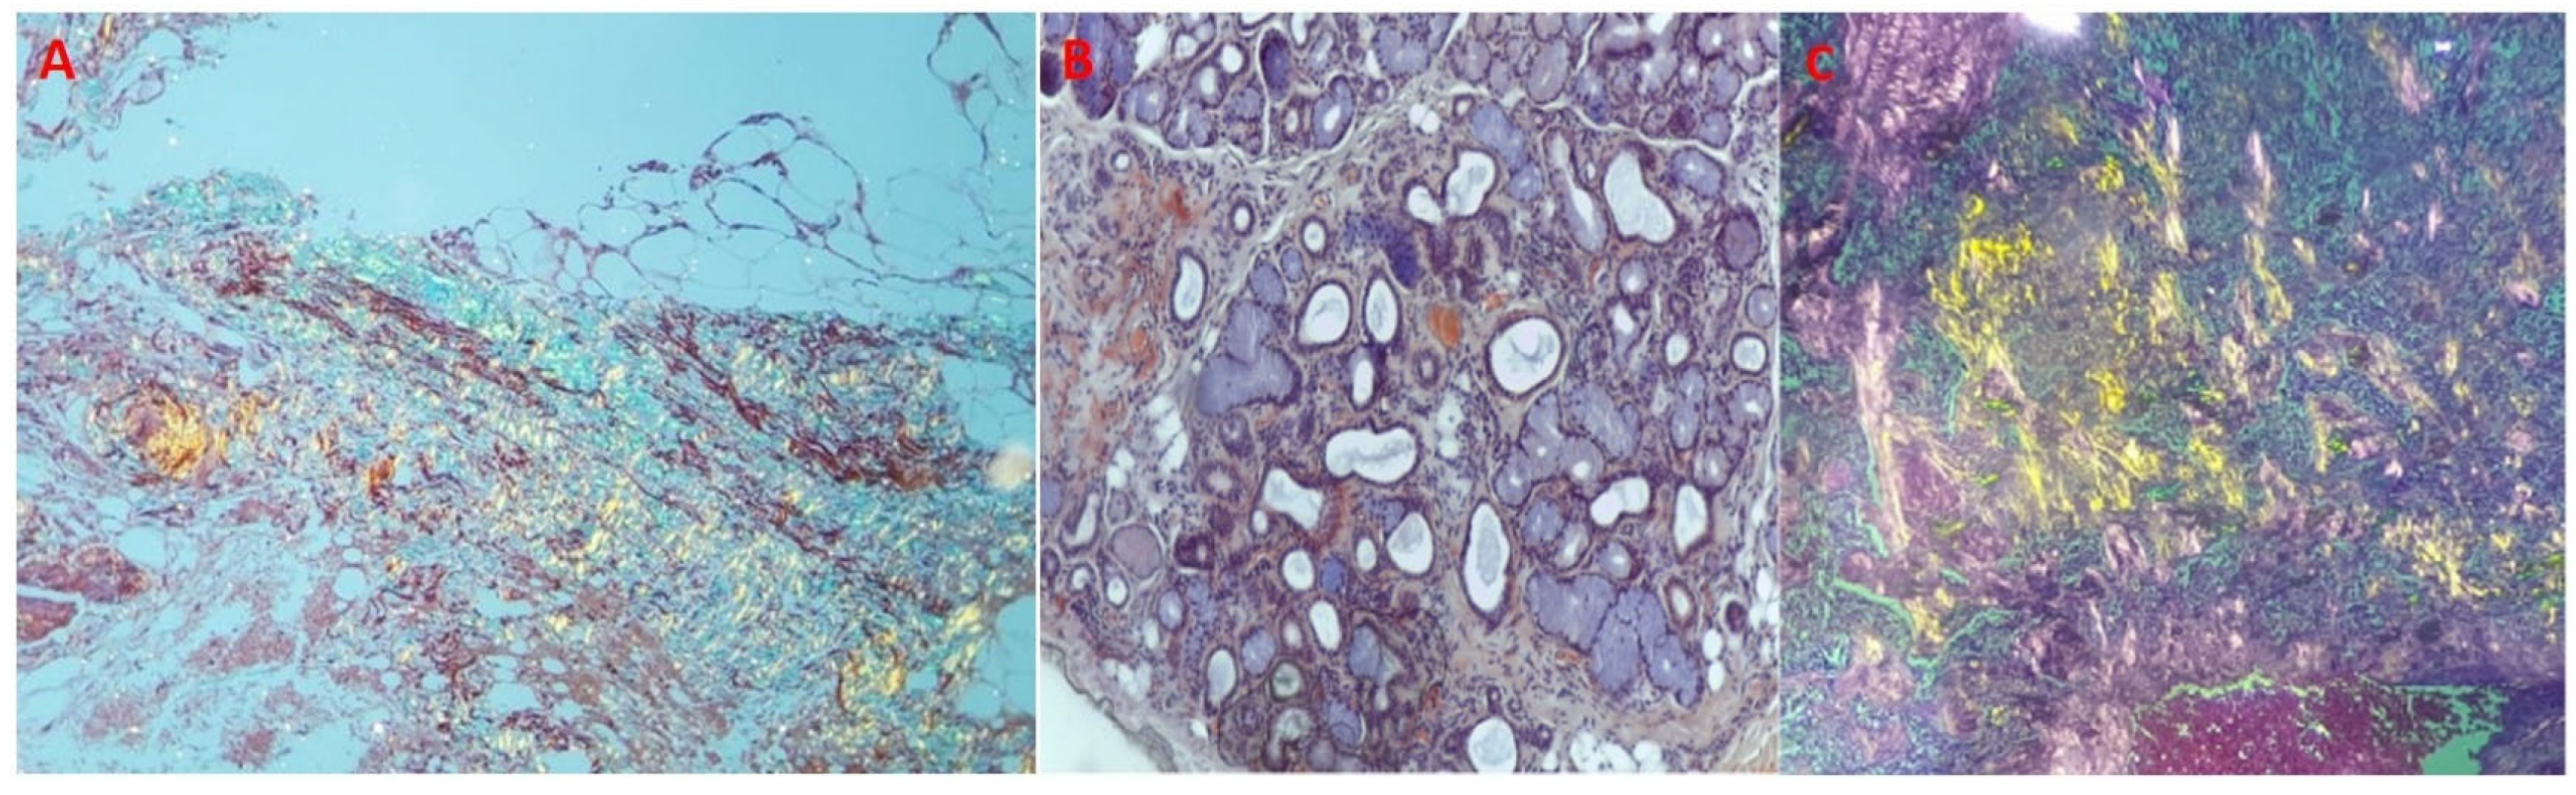

We performed scintigraphy with 99mTc-DPD and single photon emission computed tomography (SPECT) imaging, which showed grade 3 Perugini and confirmed biventricular myocardial uptake (Figure 2A,B). Furthermore, assessment for monoclonal proteins by serum and urine protein electrophoresis with immunofixation, and quantification of serum free-light chains revealed normal results. The patient underwent salivary gland and abdominal fat pad biopsies (internal protocol in 2018). The histological results were both positive for amyloid depositions (Figure 3A–C).

Figure 3. Anatomo-pathological evaluation: salivary gland and abdominal fat pad biopsies. (A) Amyloid deposits in adipose tissue showing yellow-green birefringence in polarized light—Congo red stain, polarized light microscopy 4×. (B) Small peri-glandular and perivascular amyloid deposits in a minor salivary gland. Congo red stain, 4×. (C) Amyloid deposits showing typical yellow-green birefringence in polarized light—Congo red stain, polarized light microscopy 4×.